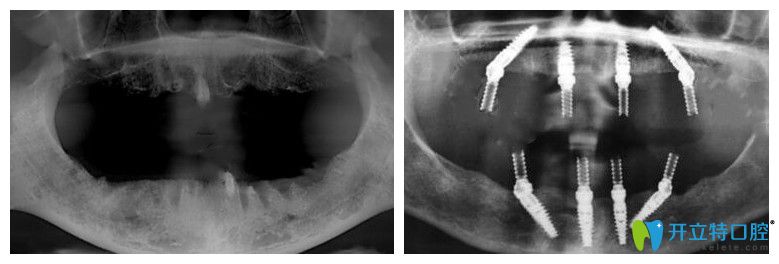

65歲,薛老師;種植前上頜牙齒全部脫落,下頜就剩下四顆殘根;之前戴過(guò)活動(dòng)假牙,但因?yàn)闀r(shí)間長(zhǎng)了戴上很容易掉,所以才考慮做全口種植牙。下面是做種植牙前后的CT片:

薛老師說(shuō)沒(méi)做種植牙前聽(tīng)別人說(shuō)價(jià)格特別貴,但是在靖江艾齒嘉口腔面診、拍片檢查后,陳濤醫(yī)生建議自己做ALL-ON-4全口種植牙,上下頜各植入4顆種植體,就能支撐全口牙冠,這種方法不僅讓自己省了很多錢,而且吃東西的咀嚼力也強(qiáng)。